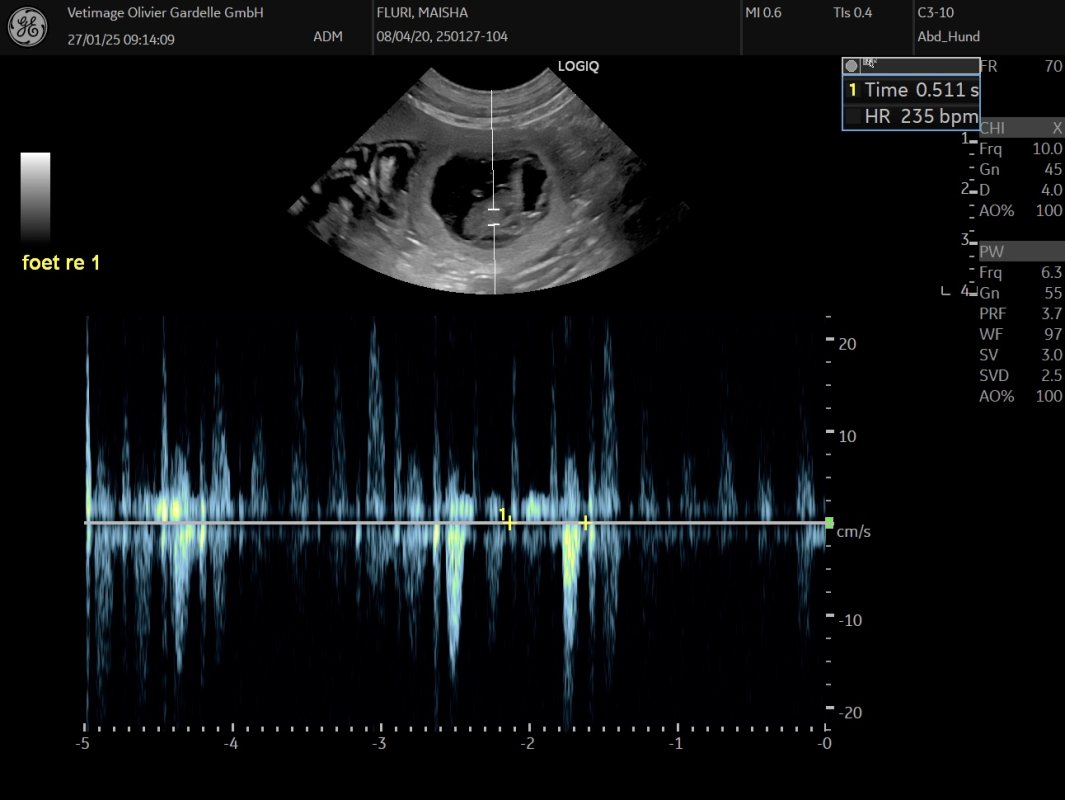

Am 24. März hat der Ultraschall gezeigt, Maisha ist trächtig 🐾❤️. Wir sind überglücklich!